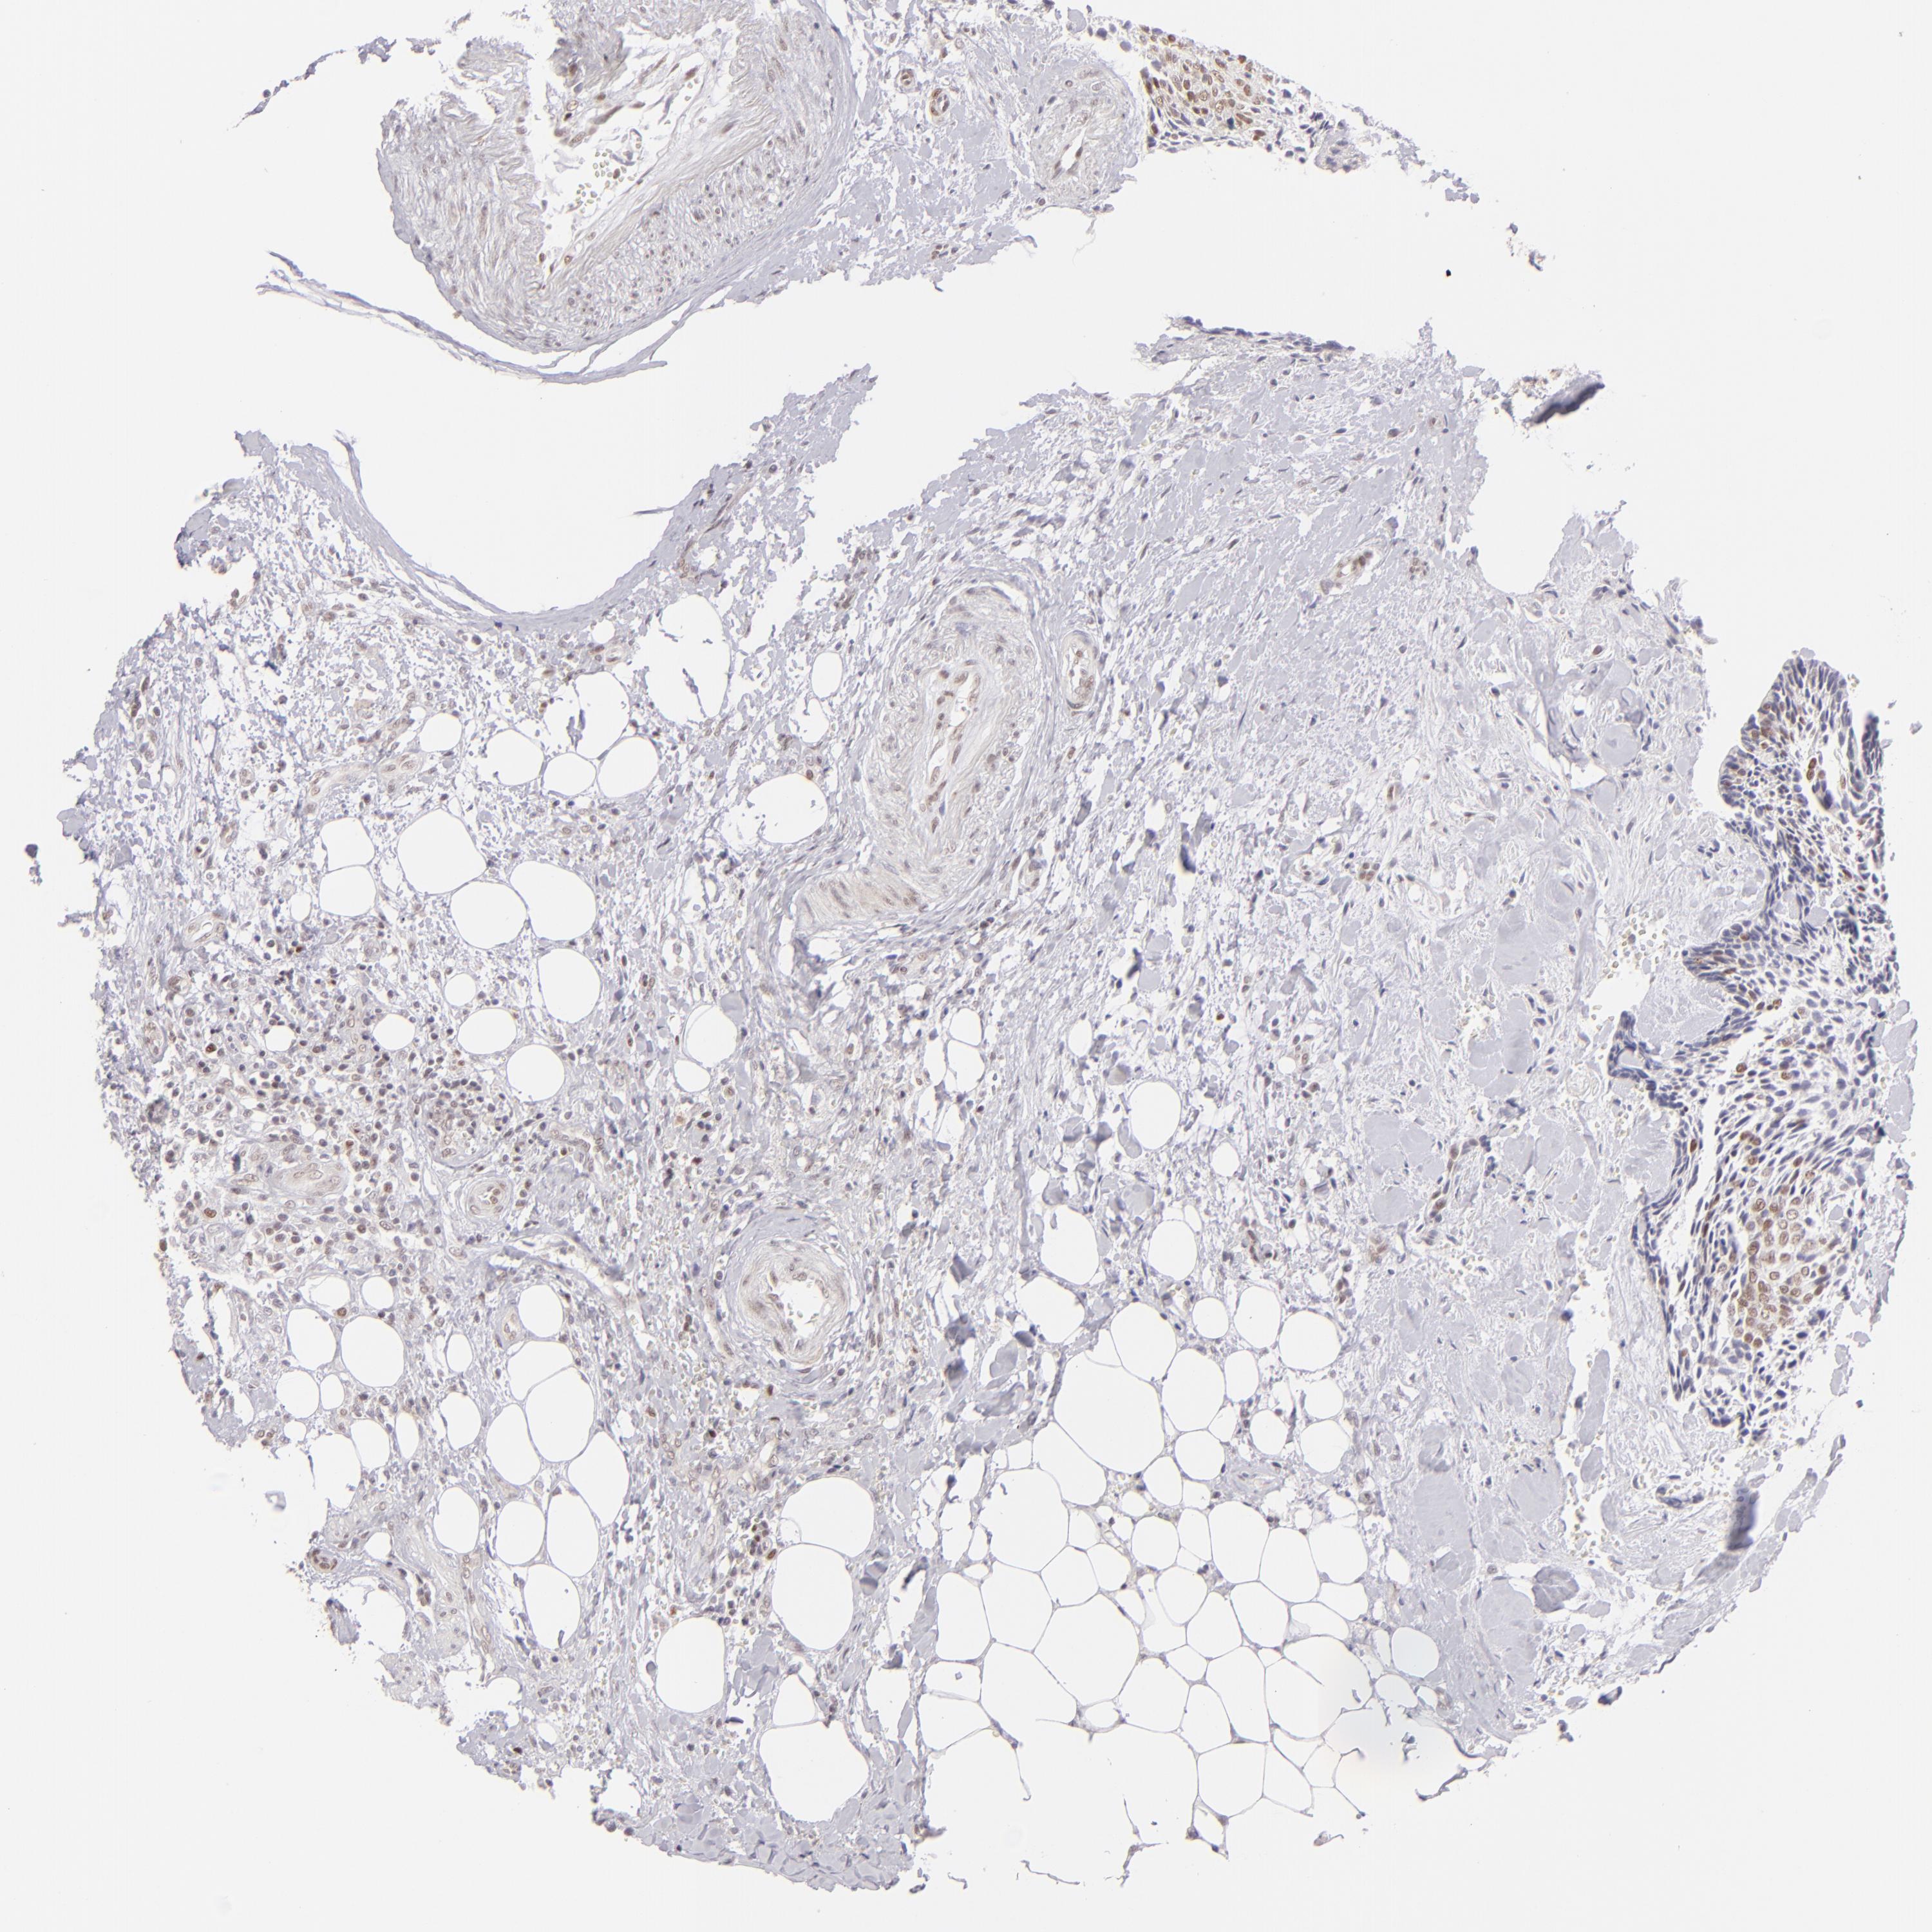

HEAD AND NECK CANCER - Protein expressioni

A mouse-over function shows sample information and annotation data. Click on an image to view it in a full screen mode. Samples can be filtered based on level of antibody staining by selecting one or several of the following categories: high, medium, low and not detected. The assay and annotation is described here.

Antibody stainingi

Antibody staining in the annotated cell types in the current human tissue is reported as not detected, low, medium, or high, based on conventional immunohistochemistry profiling in selected tissues. This score is based on the combination of the staining intensity and fraction of stained cells.

Each image is clickable and will lead to virtual microscopy that enables deeper exploration of all samples and also displays staining intensity scores, fraction scores and subcellular localization as well as patient and tissue information for each sample.

Antibody HPA064323

Squamous cell carcinoma, NOS

Adenocarcinoma, NOS

Squamous cell carcinoma, metastatic, NOS